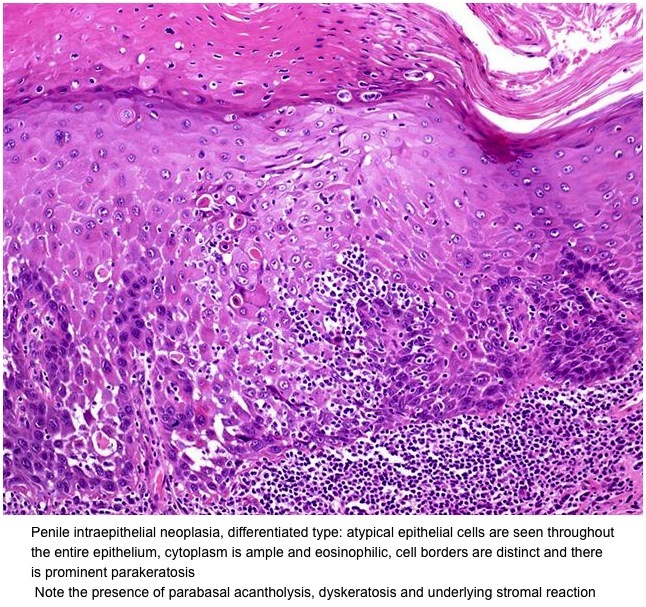

penile cancer photos download

Posts: penile cancer photos download